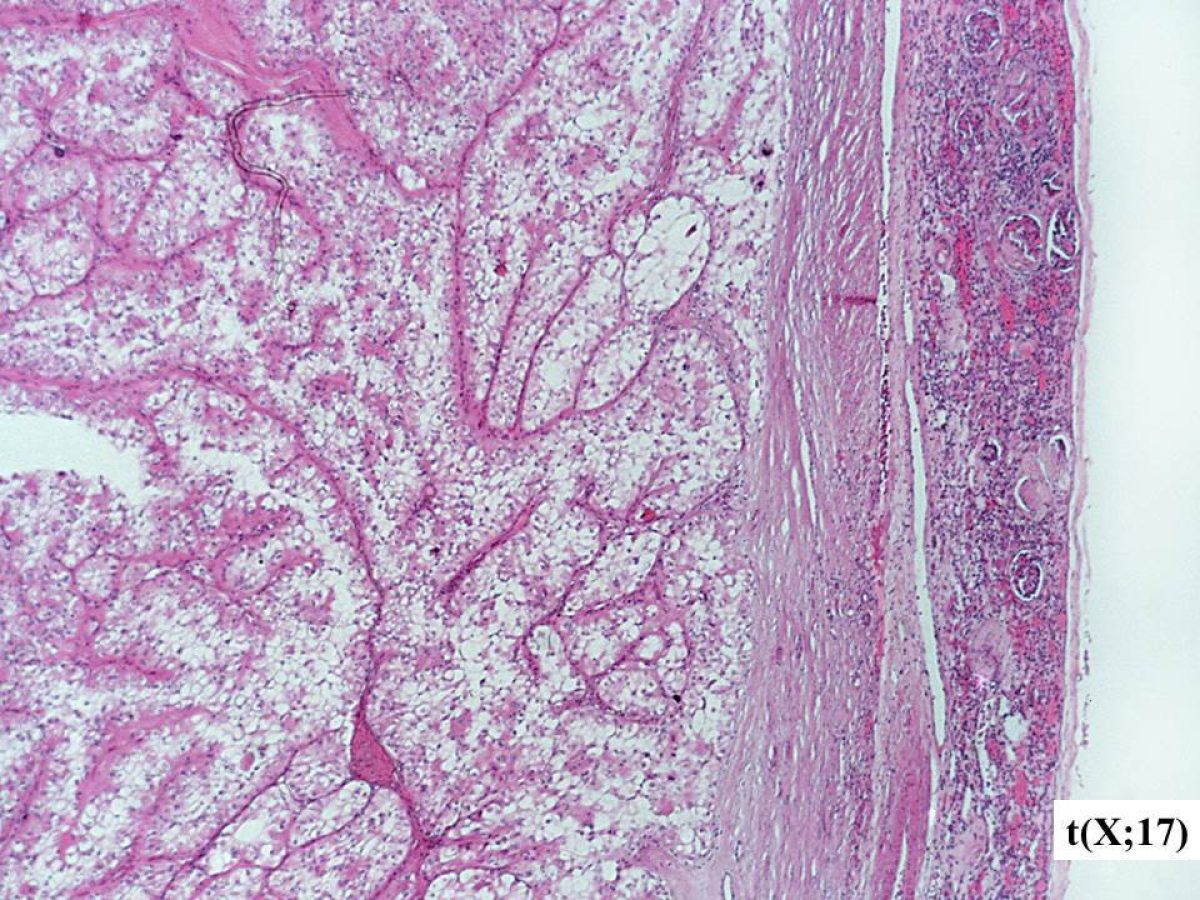

These pathology images are examples of what Translocation Renal Cell Carcinomas look like under the microscope.